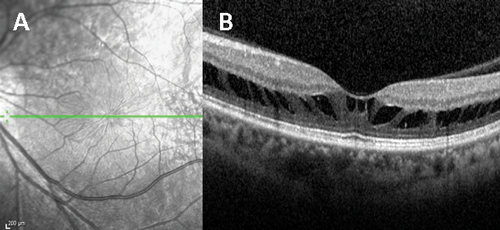

Figure 3: OCT image centered on the macula taken from a patient with achromatopsia. This image demonstrates the presence of a foveal hyporeflective zone.

The fundus appearance in ACHM is often normal but RPE disturbance or atrophy at the macula can be seen [33]. Electrophysiological assessment demonstrates reduced, or absent cone responses with normal rod responses. SD-OCT findings are variable in ACHM and have implications for anticipated gene therapy trials; outer retinal architecture may be classified as: (1) continuous inner segment ellipsoid (ISe), (2) ISe disruption, (3) absent ISe, (4) foveal hyporeflective zone (Figure 3), and (5) outer retinal atrophy [36].